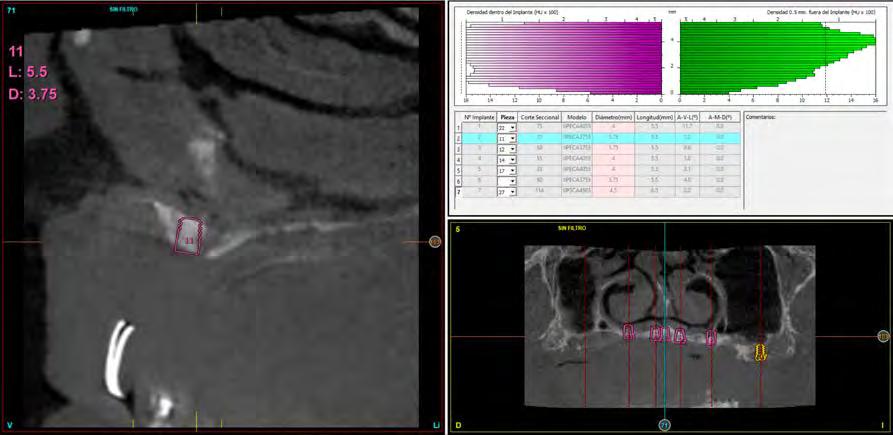

Figura 1. Diámetros y longitudes incluidos en el estudio según su posición.

Figura 2 y 3. Figuras intraorales del paciente de 67 años que acude a la consulta para rehabilitación sobre implantes superior, portador de una prótesis completa removible con una atrofia ósea evidente al ser la prótesis retirada. Figura 4. La radiografía inicial muestra una atrofia marcada en sentido vertical, que debe ser constatada posteriormente mediante un TAC así como para la planificación de la colocación de los implantes. Figura 5 y 6. Encerado diagnóstico para comenzar la planificación de la colocación de los implantes superiores guiados por la posición ideal que deben tener los dientes en la prótesis. De este encerado se realiza una guía radiológica que nos permita trasladar estas posiciones al TAC de planificación.

Fueron reclutados 6 pacientes en los que se colocaron 30 implantes para realizar rehabilitaciones completas. La edad media de los pacientes incluidos en el estudio fue de 66.75 años (+/- 5,16) y un 86.7% fueron mujeres. El 63.3% de los implantes se insertaron en el maxilar superior y el 36.7% restante en la mandíbula, formando parte de 4 rehabilitaciones

completas superiores y 3 inferiores. Todos los implantes presentaron una longitud de 5.5 m m, con diámetros comprendidos entre los 2.5 y los 5.5 mm. Las posiciones de los implantes corresponden a distribuciones biomecánicas para la realización de prótesis completas tanto en el maxilar como mandíbula (incisivos, premolares y molares). Los diámetros y longitudes de los implantes incluidos en el estudio en función de

181. Septiembre 2023 51 Rehabilitaciones completas implantosoportadas

su posición se muestran en la Figura 1.

Figura 7­9. Cortes de planificación del cone beam donde observamos la extrema atrofia vertical y la posición en la que deberían situarse los dientes con una gran discrepancia entre esta posición y la base ósea. Vemos también como se planifican implantes extracortos de 5.5 mm de longitud en todas las localizaciones. Figura 10. Radiografía panorámica tras la colocación de los implantes.

En las Figuras 2­17 se puede observar uno de los casos incluidos en el estudio.